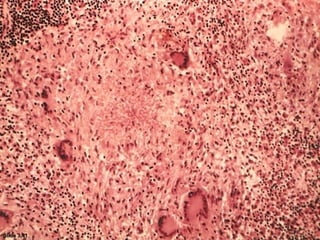

1. Caseous Necrosis 2. Epithelioid Cells 3.

Giant Cells 4. Lymphocytes 5. Fibrous cup

1. Caseous Necrosis 2. Epithelioid Cells 3. Giant Cells 4.

Lymphocytes 5. Fibrous cup

Microscopically,

1. the necrosed foci are structureless, eosinophilic, and contain

granular debris.

2. The surrounding tissue shows characteristic

granulomatous inflammatory reaction consisting of

epithelioid cells with

3. interspersed giant cells of Langhans’ or foreign body type

and

4. peripheral mantle (layer, covering, Ring, collar) of lymphocytes.

5. Fibrous cup.

Langhans Giant Cell

Caseous Necrosis

Epithelioid Macrophage

Lymphocytic Rim

Caseating granulomas